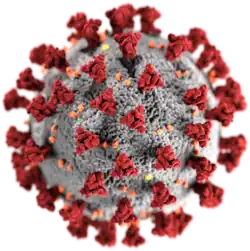

- COVID-19 pandemic: Chinese authorities first publicly confirm that there is human-to-human transmission of severe acute respiratory syndrome coronavirus 2.[57]

- 31 January – Scientists and journalists report overviews of the novel coronavirus SARS-CoV-2 outbreak, later classified as a pandemic, including on the infectability, mortality rate, incubation time, worldwide ability to contain the outbreak, and estimated time for a vaccine (along with a comparison with other similar outbreaks).[68][69][70]

−0.18-day pulse cycle.[90][91][92][93][94] - 4 February – The drugs remdesivir and chloroquine are shown to effectively inhibit SARS-CoV-2 in vitro.[95][96]

- Scientists report that bats' heightened immune responses to their viruses, of which SARS-CoV-2 is a likely example, can facilitate the evolution of rapidly-replicating viruses that likely cause enhanced virulence following emergence into secondary hosts with other immune systems such as humans. The researchers used a combination of in vitro experimentation and within-host modeling to explore the impact of the previously already well-known unique bat immunity on virus dynamics.[115][116]

- Scientists present an atomic-level image using cryogenic electron microscopy of an essential protein used to access cells by the SARS-CoV-2 novel coronavirus that is responsible for the coronavirus disease 2019 (COVID-19) and COVID-19 pandemic. This image may help in more quickly finding a cure or to develop medical countermeasures (MCMs) for the viral infection.[149][150]

- 20 February – Scientists use the world's most powerful supercomputer, SUMMIT, to screen molecules which bind to either SARS-CoV-2's spike protein or to its human ACE2 interface and publish their results, including a ranked list of compounds which may be repurposed to attenuate COVID-19, in a preprint.[154][155]

- Initial phase 1 testing of a Coronavirus vaccine from biotechnology company Moderna is reported to start soon.[173][174]

- Scientists report that they have identified a second enzyme in the cell membrane of lung cells essential for entry of SARS-CoV-2 into the cells after the enzyme ACE2 has been identified earlier by other researchers. They found that the protease TMPRSS2 is split by the virus' spike protein to enter the cell and that the TMPRSS2-inhibitors Camostat and, in a second report by other researchers on 18 March, Nafamostat may be potential treatments as they reduced the probability of the virus entering cells in vitro.[211][212][213]

- Chinese news announces that the first confirmed case of the COVID-19 disease, caused by the SARS-CoV-2 virus, was traced back to a 55-year-old patient in Hubei province, and was reported in a Chinese newspaper on 17 November 2019.[248] To date (14 March 2020), 67,790 cases and 3,075 deaths due to the virus have been reported in Hubei province; a case fatality rate (CFR) of 4.54%.[248]

- 17 March – Scientists report that the novel SARS-CoV-2 virus, which causes the COVID-19 disease, and is responsible for the COVID-19 pandemic, originated naturally, and not otherwise,[268][269] although Chinese medical researchers, including Shi Zhengli, in Wuhan, China, were studying bat coronaviruses in ways that included modifying virus genomes to enter human cells, as early as 2014,[270][271] in testing laboratories that were determined to have significant safety issues by U.S. scientists in 2018.[272][273][274]